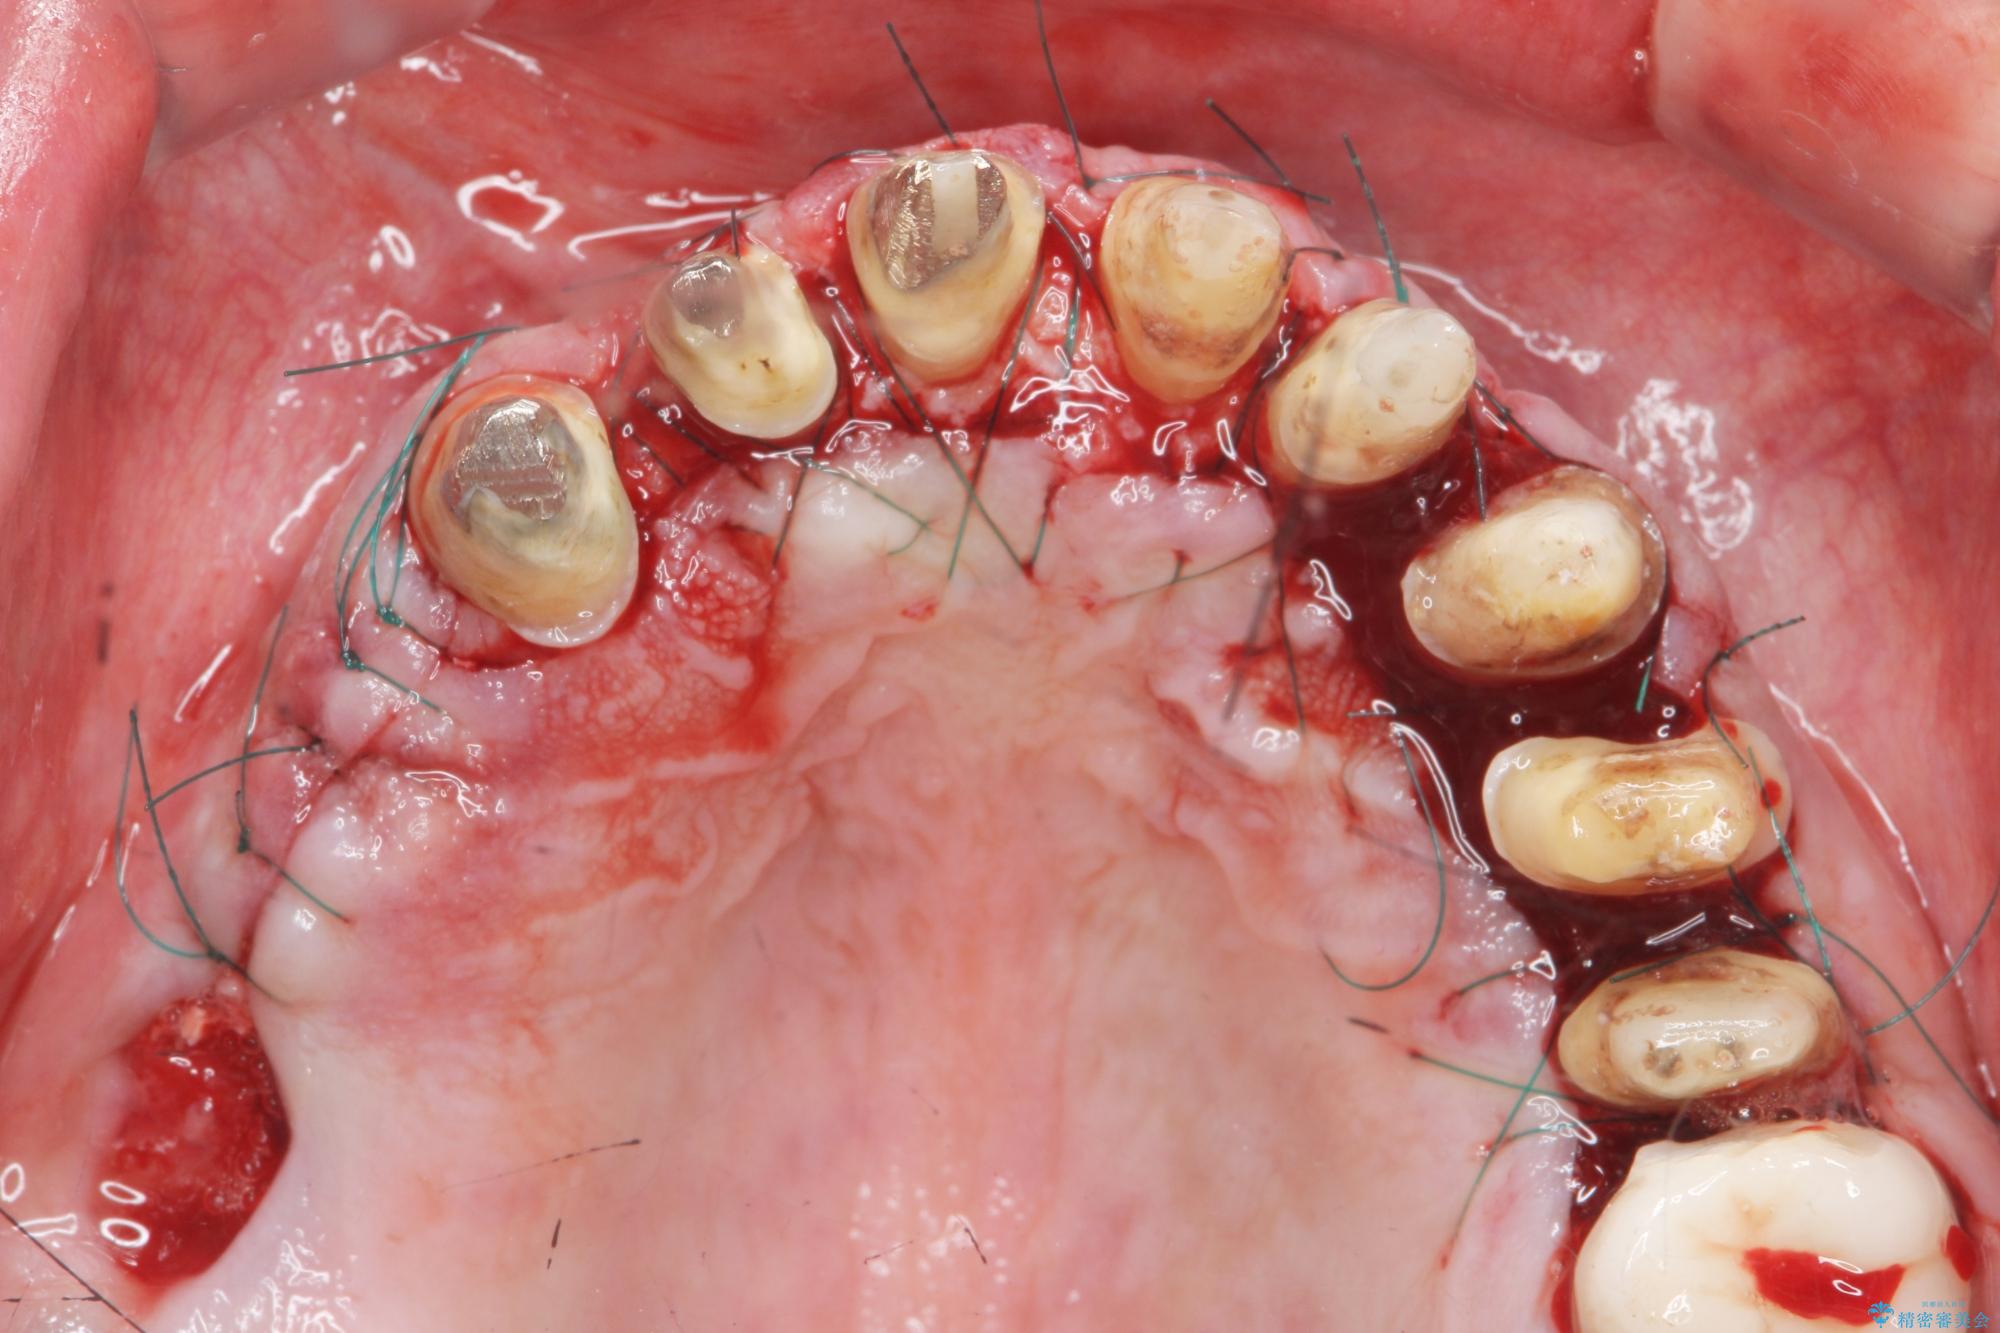

- 「セラミック治療を他院で受けたが、それ以来歯ぐきが腫れ違和感がある、改善してほしい。」と歯ぐきの状態改善を希望され来院されました。

歯周組織検査を行うと歯ぐきからは容易に出血し、X線検査より歯とセラミッククラウンの適合が悪い(ピッタリと合っていない)状態が示唆され、歯ぐきの炎症を惹起している状態でした。

セラミッククラウンを除去し仮歯を装着し、歯周外科手術を行い歯ぐきの状態を改善したのち、適合の良いセラミッククラウンを再作製をする治療計画としました。

- 90.2万円(ジルコニアクラウン×6・仮歯×6 ・歯周外科手術)費用は治療当時の料金となります